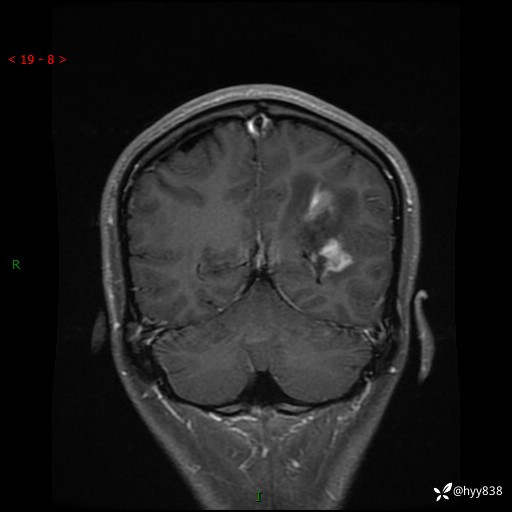

颅脑MRI平扫+增强